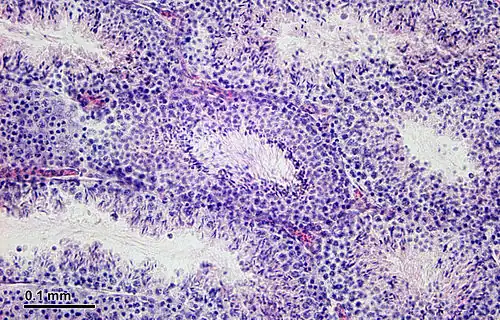

La spermatogenesi avviene nel parenchima dei testicoli (o didimi) e più precisamente nell'epitelio germinativo dei tubuli seminiferi, condotti a fondo cieco dal diametro di 150-200 µm che confluiscono nei tubuli seminiferi retti (Russell et al. 1990). I tubuli retti finiscono poi per anastomizzarsi nella rete testis da cui partono 15-20 dotti efferenti che si immettono nell'epididimo che continua poi nel canale deferente.

La parete di questi tubuli seminiferi è formata da cellule di sostegno, denominate cellule del Sertoli e svariate cellule germinali rappresentate dagli elementi che compongono le varie tappe della spermatogenesi[9].

Le cellule di Sertoli non fanno parte delle cellule germinali ma costituiscono le cellule di sostegno del tubulo seminifero. Esse sono infatti appoggiate sulla lamina basale del tubulo e danno direttamente nel lume. Fra una cellula e l'altra avvengono le varie tappe della spermatogenesi e, quindi, in una sezione di tubulo seminifero si potranno notare cellule di Sertoli con intercalati i vari spermatogoni, spermatociti, spermatidi e spermatozoi in via di differenziazione o maturazione.[9]